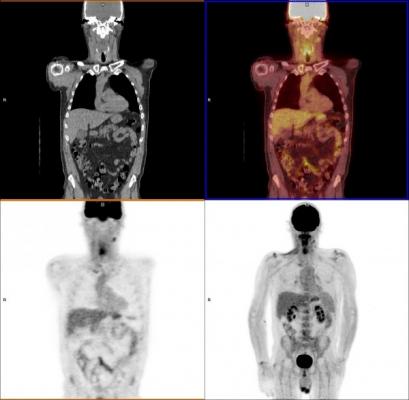

PET-CT画像診断マニュアル Clinical PET and PET/CT | SpringerLinkの詳細情報

Clinical PET and PET/CT | SpringerLink。fmed-09-896494-g001.jpg。医療関係のみなさまへ 日本医科大学健診医療センター。 現在、1名がこの商品を検討中です

PET-CT画像診断マニュアル

PET-CT画像診断マニュアル